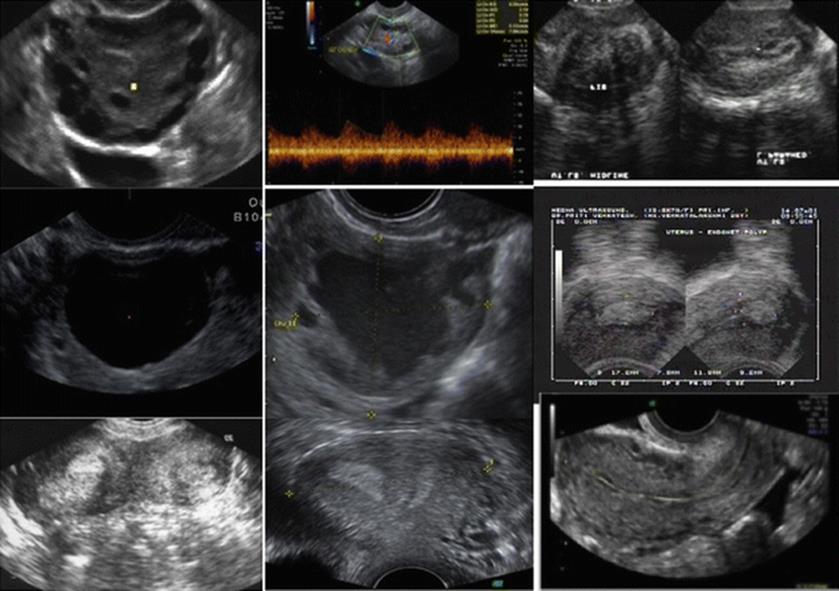

The morphology of the endometrium in the different phases of menstrual cycle is illustrated below (Fig. 2.17).

Fig. 2.17

Morphology of endometrium in the different phases of menstrual cycle. (a) Preovulatory, (b) at ovulation, (c) post ovulation

· Early proliferative phase – translucent and thin on either side of mid-line echo

· Late proliferative phase – increase in thickness with a hyporeflective area in the center

· Following ovulation – shrinks in thickness, becomes dense echogenic on either side of mid-line echo

An association has also been noted between the ultrasound endometrial texture, echogenic patterns, and serum hormonal (estradiol and progesterone) levels. In IVF cycles, a preovulatory, echogenic, and homogeneous pattern has been associated with premature rise in progesterone levels, probably due to high LH levels in the early proliferative phase or premature secretion of LH, especially in the antagonist flexible protocol. This is due to the presence of high estradiol levels, which are related to multifollicular development. Endometrial hyperechogenicity prior to ovulation is a poor prognostic factor for pregnancy (Fig. 2.18a). On the other hand, women with a triple line pattern on the day of oocyte retrieval conceived in 80.0 % of the cases (Fig. 2.18b).

Fig. 2.18

(a) Hyperechogenic endometrium, (b) triple-line pattern

The endometrial pattern with an outer hyperechogenic and inner hypoechogenic layer on the day of oocyte retrieval had predictive value of IVF treatment [31]. Homogenous and hyperechogenic sonographic endometrial pattern had a predictive value of 100 % for a nonconceptional cycle, whereas multilayered endometrium was visualized in conception cycles [32].